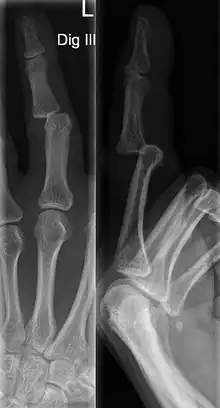

DIP Dislocation

PIP Dislocation

Dislocations can be categorised based on location and type. The finger can be split into three bones and two joints in an alternating order. From the fingertip to the knuckle, these are as follows; distal phalanx, distal inter-phalangeal (DIP) joint, middle phalanx, proximal inter-phalangeal (PIP) joint, and proximal phalanx. DIP dislocations are much less common than PIP dislocations,[2] due to the "stability provided by strong collateral ligaments, palmar plates, and tendinous insertions, as well as the short lever arm of the distal phalanx".[7] Dislocations can be categorised based on the direction that the fingertip moves in relation to the knuckle, be it in the direction of the palm (volar dislocation), or the direction of the back of the hand (dorsal dislocation). Of the two, dorsal dislocations are more common.[3] If reduction has been attempted, an x-ray of the dislocation should appear concentric if successful.[2] However, if there is a fracture present, there will be a misalignment of the joint, which will be evident from the radiograph.[2] Bach suggests a referral to a hand surgeon if a misalignment is present.[2]